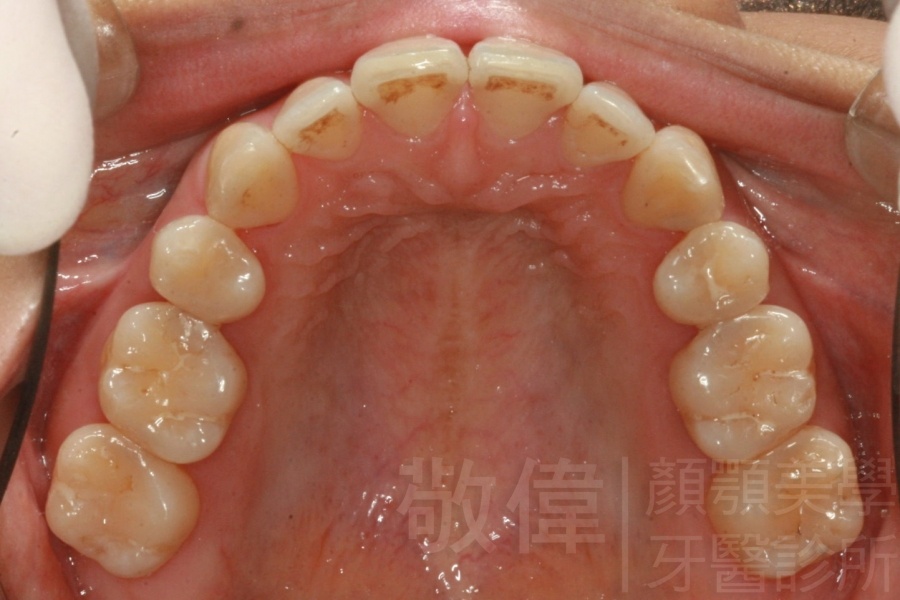

齒顏矯正/戽斗、亂牙、爛牙,變身 免植牙的健牙美女

變臉矯正,原來戽斗妹跟大歪臉變成自信正妹

經由本院3D數影X光影像儀分析、與3D齒顎顏矯正技術,再配合口腔顎面正顎專科醫師施以正顎手術治療,雙方共同合作,使患者臉部外觀有很好的改善,大歪變小歪,產生了天南地北的大改變,她的人生也整個變得不一樣。